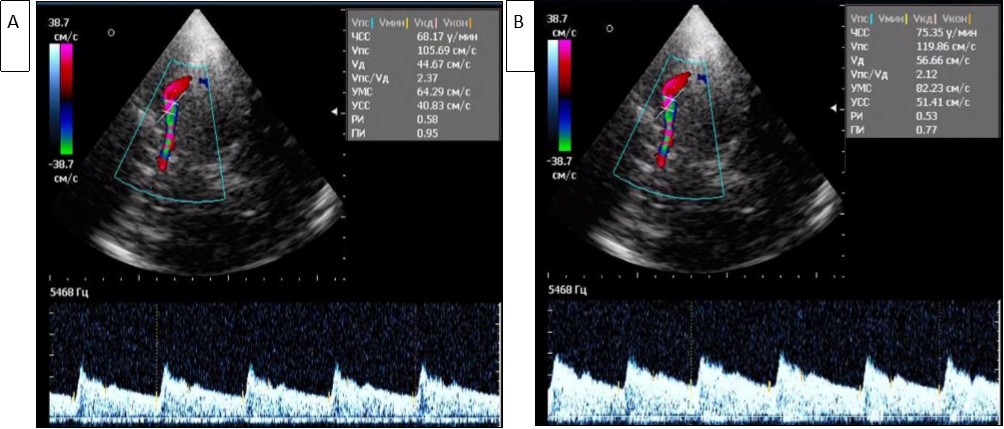

The asymmetry of the maximum systolic blood flow velocity (Vs) in the paired arteries within 20-30% was considered a violation of cerebral hemodynamics, which was detected in 38.7% of patients. An increase in Vs was noted in MCA in patients with Ch TTH and FE TTH compared with the control group (Figure 1, Figure 2A and B).

Figure 2.Registration of blood flow in the left (A) and right (B) middle cerebral arteries in triplex mode (A). High and asymmetric Vs (105 cm/s and 119 cm/s) are determined in the middle cerebral arteries.